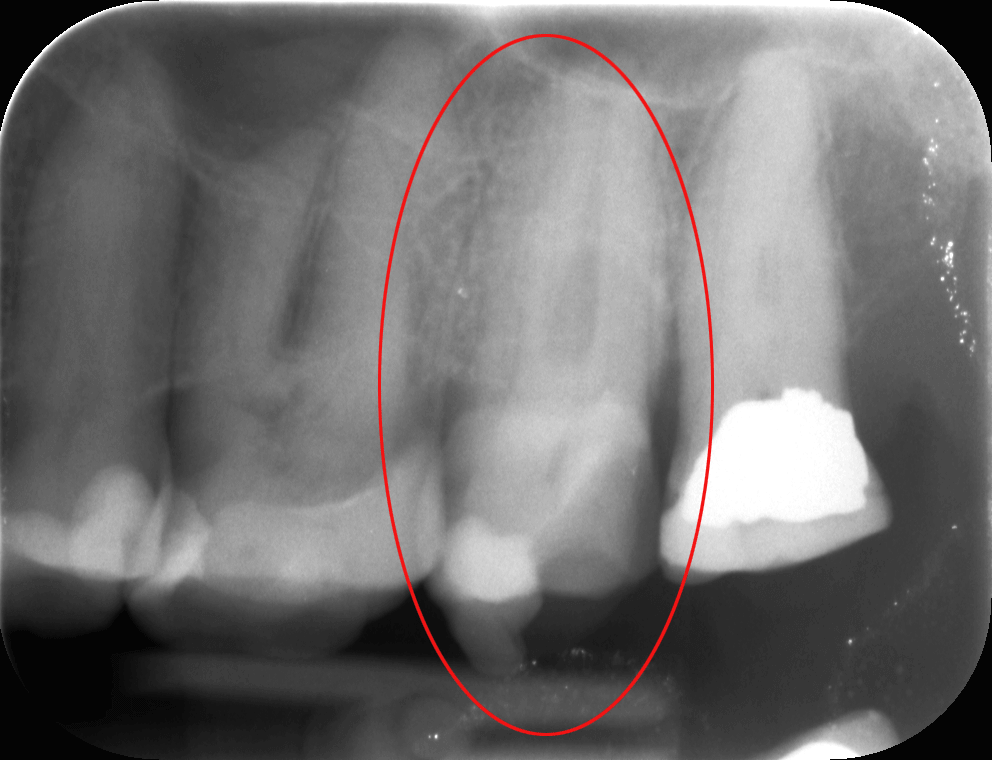

A mikroszkópos feltárás során egyértelműen kivehető volt a 4. csatorna, amit feltártunk, kitisztítottunk, így a gyökértömésről készített kontrollfelvételen (2. kép) már a 4. csatorna teljesen elkülönülő lefutását is nyomon követhetjük. Ha nem mikroszkóppal gyökérkezelünk, akkor ennek a csatornának a megtalálására, kitisztítására elenyésző az esély, így a fog is panaszos maradhat, góccá válhat, és eltávolítása előbb-utóbb indokolttá válik.

mikroszkópos gyökérkezelés után